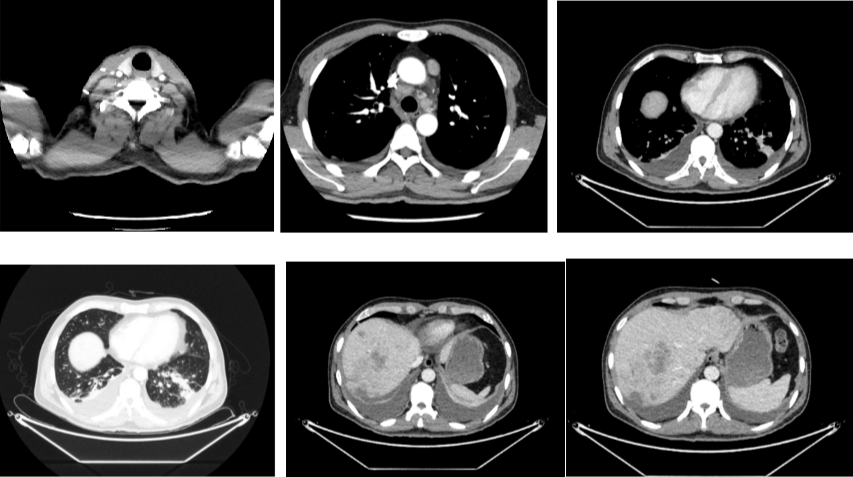

外院CT检查提示:1、两肺多发斑片状、结节影,性质待定,转移瘤?2、纵隔内多发肿大淋巴结;3、肝实质多发稍低密度影,性质待定(转移瘤可能性大)

2018-03-08 PET/CT示:胃癌(?)并全身多发淋巴结转移、肝脏多发转移、双肺上叶多发转移;

2018-11-14 CT(8周期化疗后):PD?

2018-11-19 PET/CT

胃壁代谢稍增高但未见明确的肿物,肝内低代谢结节考虑转移瘤治疗后活性减低,纵膈及右肺门两个淋巴结代谢增高,考虑转移瘤活性尚存、左侧颞骨局部骨质破坏并代谢增高,考虑转移瘤。